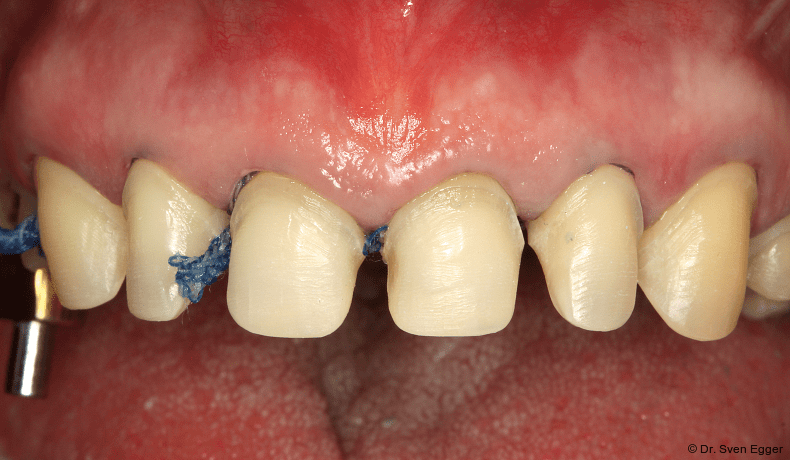

- Zweifache Abdrucknahme der präparierten Zähne mittels Doppelfadentechnik: Einbringen eines ersten, getränkten (Racestyptine solution, Septodont) Fadens (Ultrapak 0, Ultradent), über welchen ein zweiter getränkter Faden größeren Durchmessers gelegt wird (Ultrapak 1, Ultradent). Ca. zehn Minuten Wartezeit bis zur Abdrucknahme mit den gelegten Fäden.

- Die Abdrucknahme erfolgt nach Entfernung des zuletzt gelegten Fadens (der zuerst gelegte Faden geringeren Durchmessers verbleibt im Sulkus) mittels eines A-Silikons in Doppelmischtechnik einzeitig: Umspritzung der präparierten Zähne mit dünnfließendem Material (Express Ultra-Light Body, 3M Espe) und Einbringen des schwerfließenden Materials, (Express Penta Putty, 3M Espe) in einen Abdrucklöffel (Rim Lock, DeTrey; Abb.13).